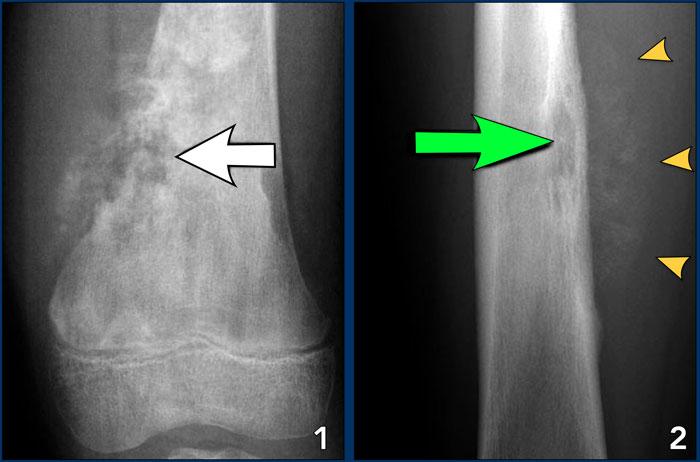

Hình ảnh

Phản ứng màng xương lành tính trong u xương dạng xương.

Mũi tên lớn chỉ phản ứng màng xương đặc.

Mũi tên nhỏ chỉ ổ tổn thương trung tâm.

Aggressive periosteal reaction (2)

- Ung thư xương (Osteosarcoma) với phản ứng màng xương gián đoạn và tam giác Codman ở phần gần (mũi tên đỏ).

Có sự hình thành xương màng xương vuông góc với xương vỏ và sự hình thành chất nền xương lan rộng do chính khối u tạo ra. - Ewing sarcoma với phản ứng màng xương dạng lớp mỏng và gián đoạn khu trú. (mũi tên trắng)

- Nhiễm trùng với phản ứng màng xương nhiều lớp.

Lưu ý rằng viêm màng xương có tính chất xâm lấn, nhưng không xâm lấn như trong hai trường hợp còn lại.